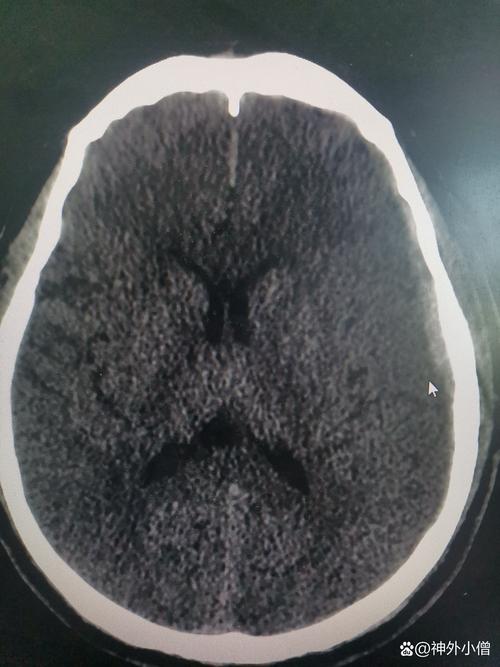

- CT扫描:

- 早期(6小时内)可能看不出明显异常,或者仅见密度轻微降低。

- 24-48小时后,梗死区域和周围的水肿带会表现为低密度区域,边界不清,像一个“模糊的阴影”。

- MRI扫描(更敏感):

- DWI(弥散加权成像):在超早期(数分钟)就能发现异常,显示为高信号,代表细胞毒性水肿。

- T2加权像 和 FLAIR(液体衰减反转恢复):在发病数小时后,梗死灶和周围的血管源性水肿带会显示为明显的高信号,FLAIR序列能更好地显示靠近脑室和脑表面的白质病变。

- T1加权像:梗死区域和水肿带通常表现为低信号。